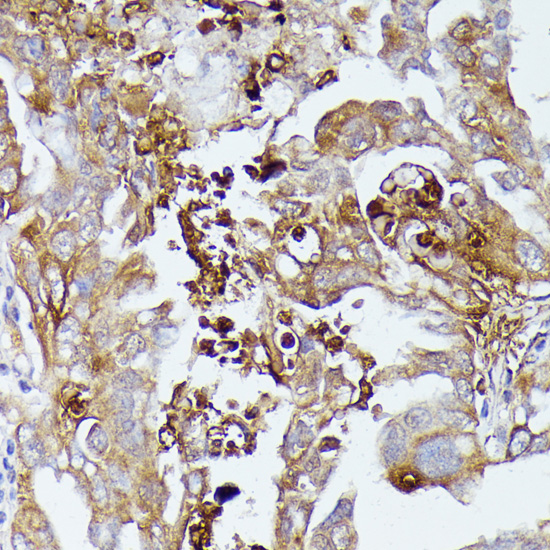

Immunohistochemistry of paraffin-embedded human lung cancer using CD52 at dilution of 1:100 (40x lens).